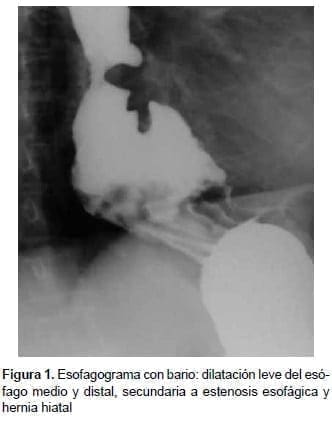

Mediante un esofagograma con bario, se observó dilatación leve del esófago medio y proximal, secundaria a la presencia de una hernia hiatal (figura 1). Inicialmente, se le dio tratamiento sintomático con un inhibidor de la bomba de protones y se le hizo seguimiento ambulatorio.